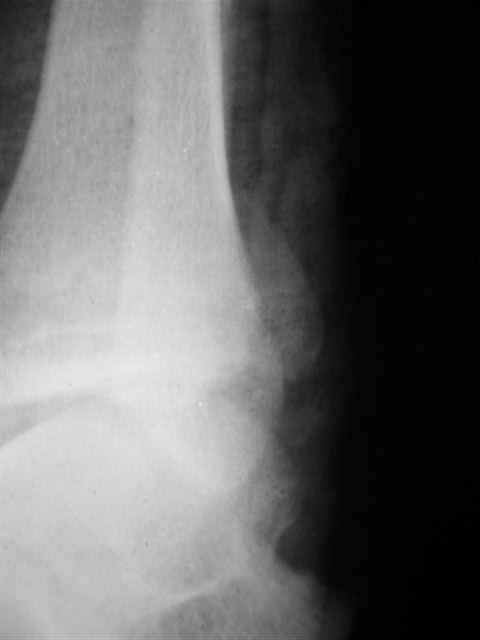

Re: открытый перелом мыщелков бедра, латерального

Я предупреждал, что ничего сверхъестественного. Каюсь, что одна из спиц прошла несколько дальше, чем нужно было, но главное - перелом стабилизирован и больной работает суставом в полном объёме, несмотря на представленную раннее травму коленного сустава.